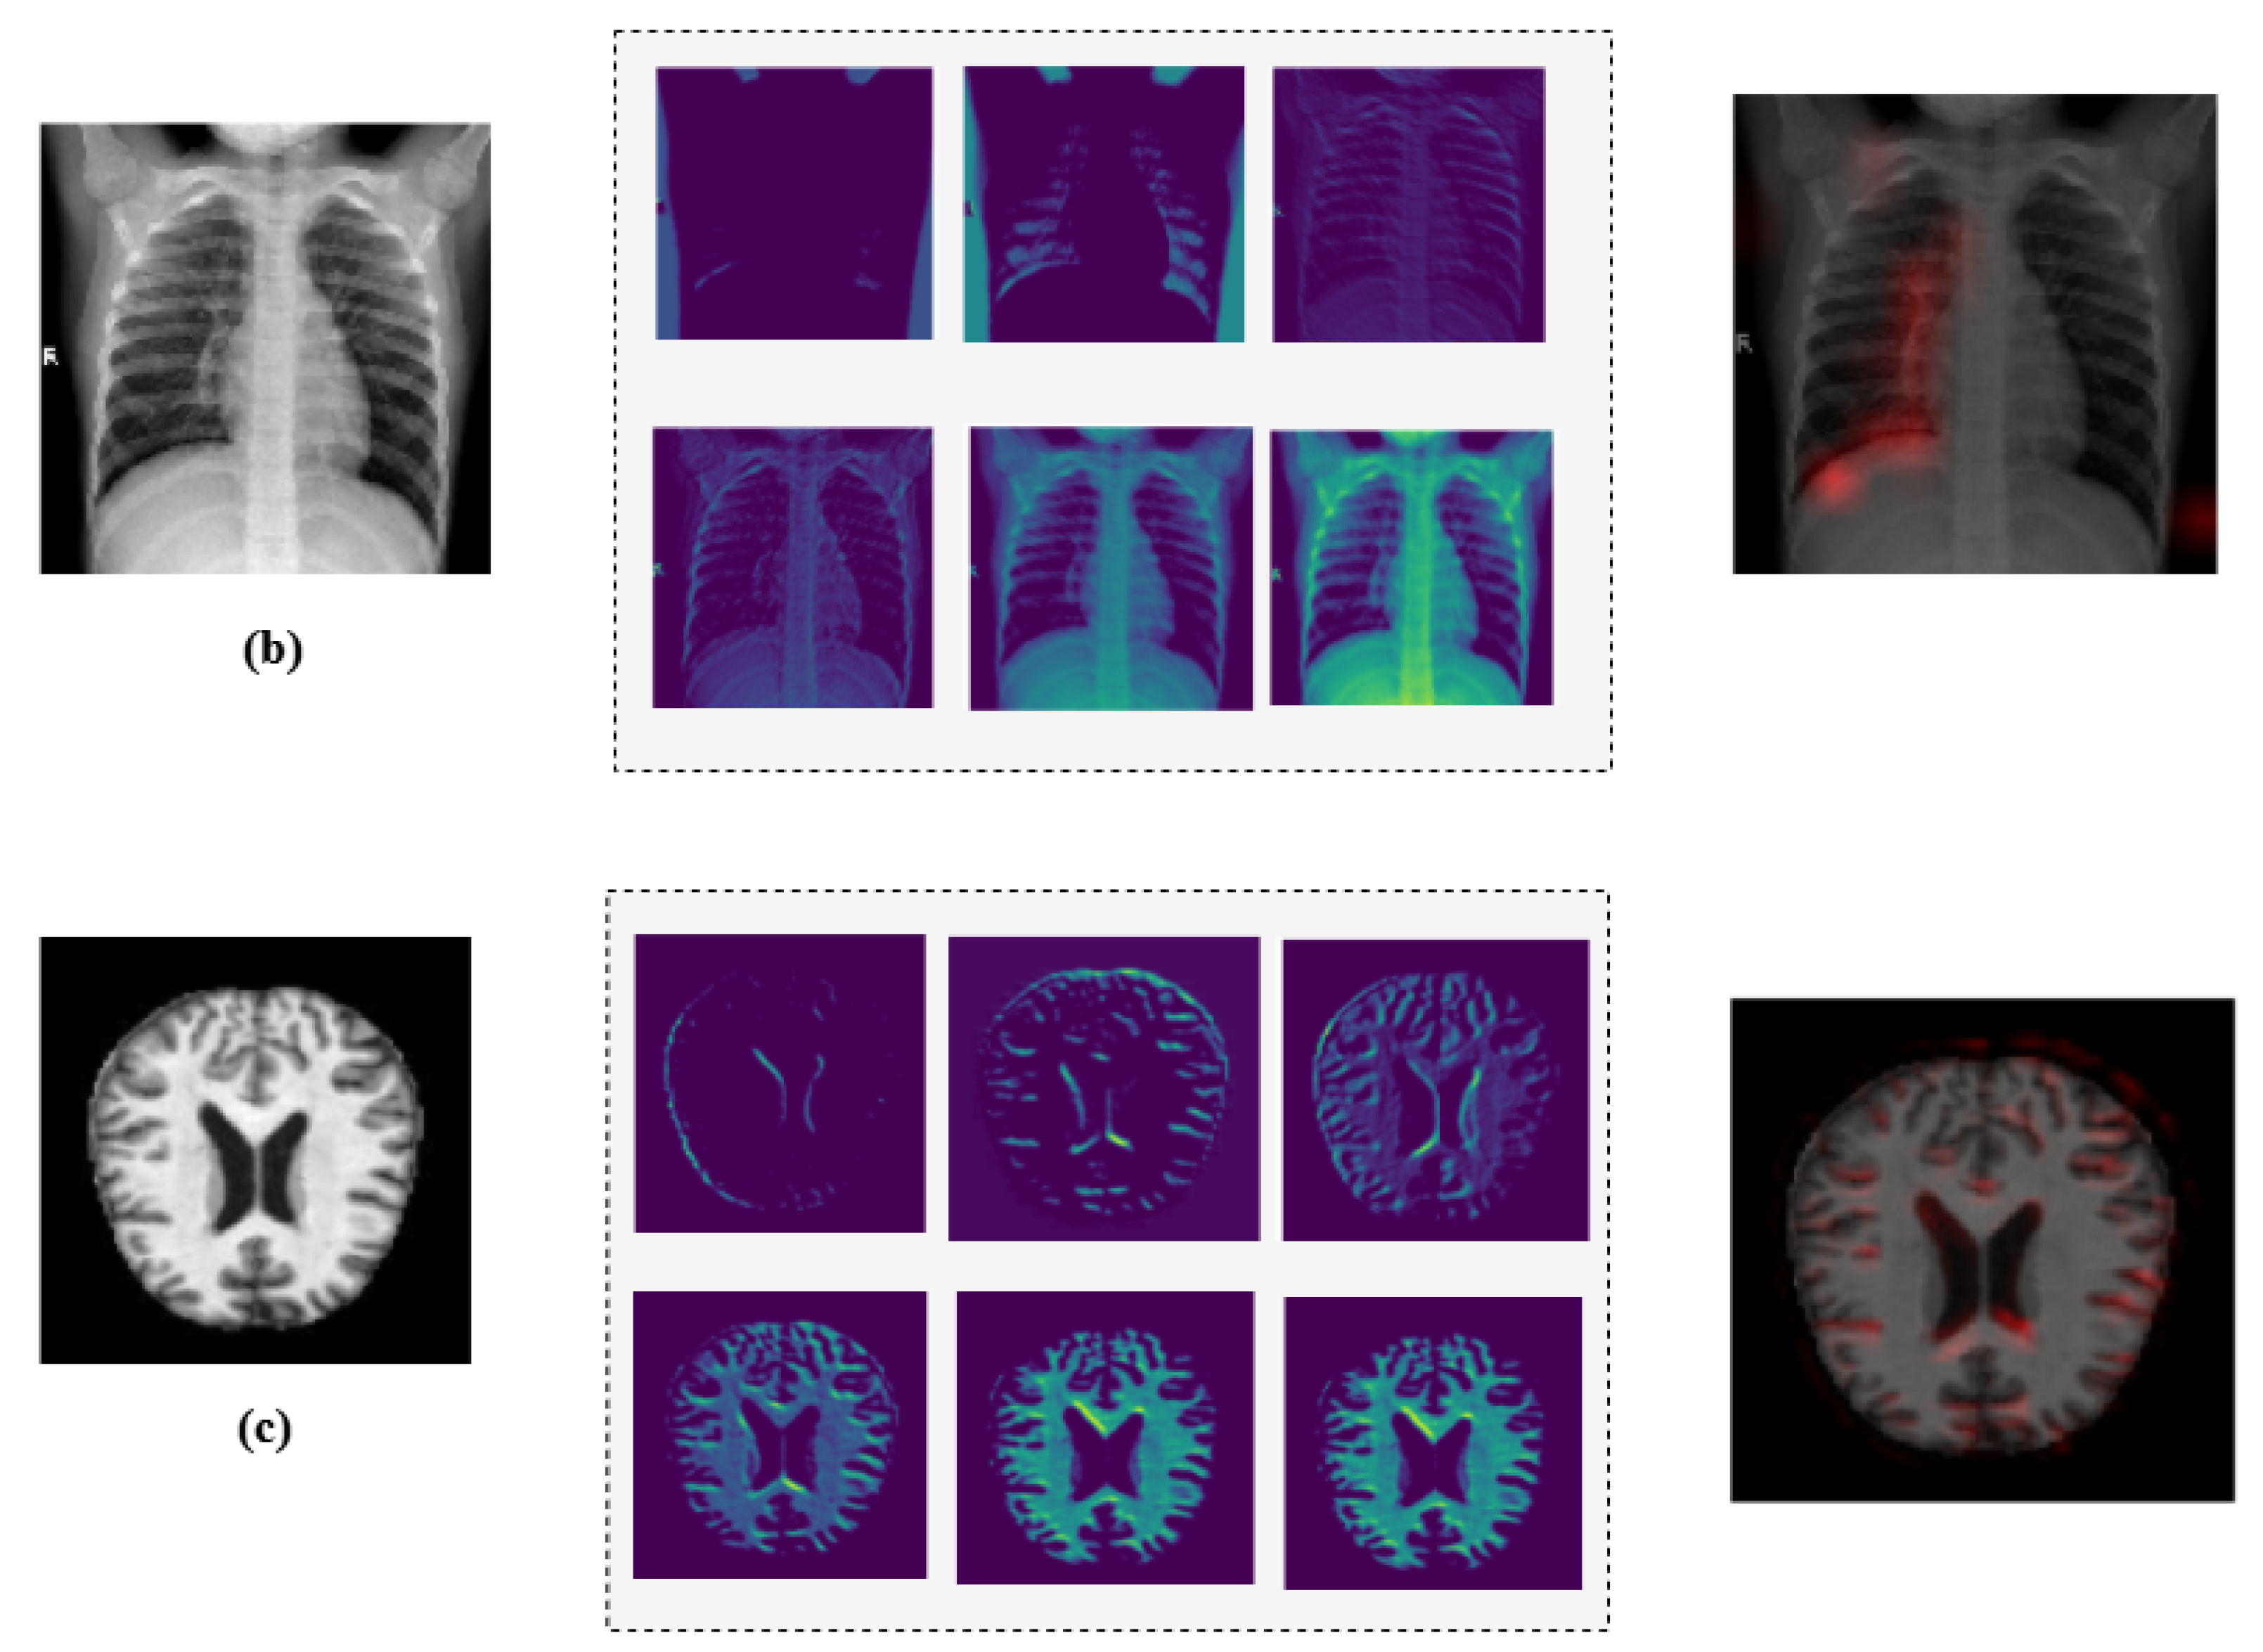

4.1. Model Interpretability via Explainable AI

Additionally, we employed Grad-CAM heatmaps to visually explain MediVision’s decision-making process across representative medical imaging datasets, namely (a) bone fracture multi-region, (b) chest X-ray, and (c) Alzheimer’s disease, as illustrated in Figure 24. These heatmaps highlight the image regions that contribute most significantly to the model’s class predictions. Since MediVision performs classification rather than segmentation, the Grad-CAM heatmaps emphasize discriminative features learned by the model, rather than anatomically precise regions of interest. The intermediate convolutional layers act as feature detectors, and the resulting activations, visualized as intensity-based overlays, reveal where the model focuses during classification. This visual interpretation validates that MediVision accurately identifies significant disease characteristics within the input image. The consistency of highlighted regions across these representative datasets supports the model’s generalizability and its ability to detect subtle disease patterns across diverse imaging modalities. These findings demonstrate MediVision’s potential to enhance diagnostic accuracy and reduce human error in clinical settings.

Figure 24.

Grad-CAM heatmap visualization showing important regions (in red) for disease classification across representative datasets: (a) bone fracture multi-region, (b) chest X-ray, and (c) Alzheimer’s disease.